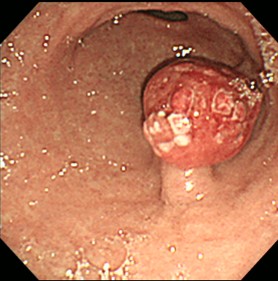

胃がん

胃粘膜の細胞が悪性腫瘍のがん細胞へと変化し、増殖していきます。日本では男女ともに胃がん患者数は減少傾向にありますが、それでもがんの患者数ではいまだに上位を占めており、年間10万人あたり約100人が日本で新たに胃がんと診断されています。国立がん研究センターが2017年に発表したがん死亡予測では、全がんの死亡数を378,000、そのうち胃がんの死亡数は47,400としています。男女とも胃がんが5位までに入っており、男性に多い傾向があります。早期には自覚症状がほとんど現れず、進行すると胃潰瘍などの胃疾患と共通の胸痛、膨満感、食欲不振などの症状を現します。早期発見のためには症状がまだない段階で定期的に胃カメラ検査を受ける必要があります。早期発見できれば適切な治療により、お仕事に支障なく完治可能です。